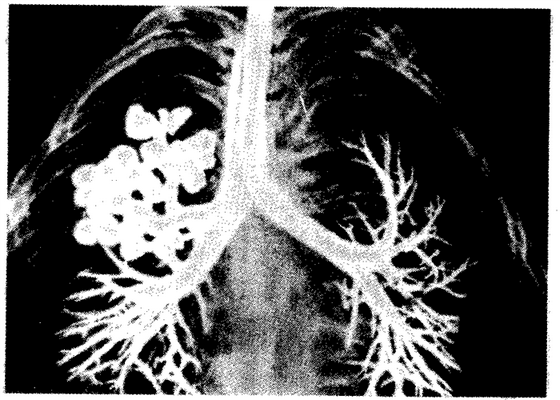

Рис. 14.26.Кистозная гипоплазия легкого